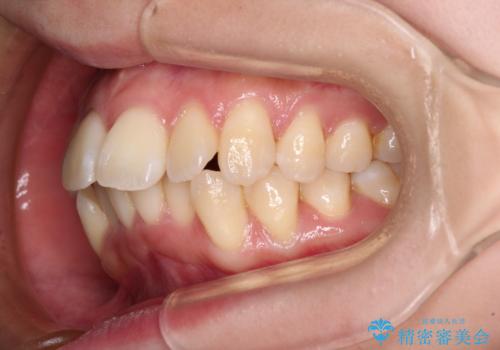

- 前歯の出っ歯と口元の閉じにくさを気にして来院された患者様です。

口元を積極的に引っ込めるために、上下左右の小臼歯4本を抜歯し、目立たないワイヤー装置にて矯正治療を行うこととしました。

上下前歯の歯軸の角度が大きく改善され、お口を閉じたときに顎先に認められた梅干し様の皺も改善されました。